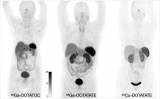

FDA批准的首个镓放射性药物示踪剂68Ga-Dotatate用于神经内分泌肿瘤的PET成像

美国食品和药物监督管理局(FDA)批准使用68Ga-Dotatate,一种用于正电子发射断层扫描(PET)成像的放射性诊断剂,以定位成人和儿童患者中的生长抑素受体阳性神经内分泌肿瘤。